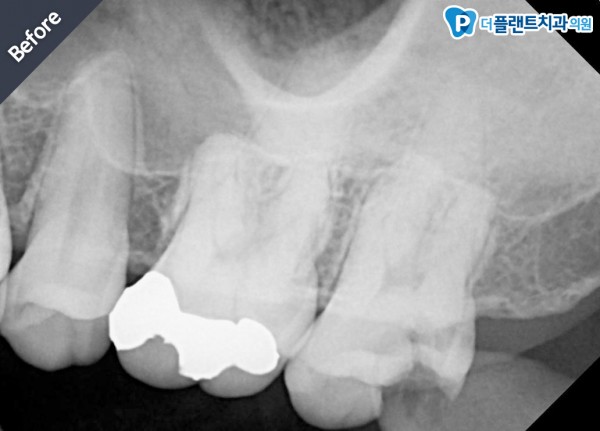

•치료명 : 구치부 신경치료

•치료내용 : 치아의 심한 우식으로 인한 치아파절로 신경이 노출된 상태였습니다. 4개의 신경관 충전하여 치료하였습니다.